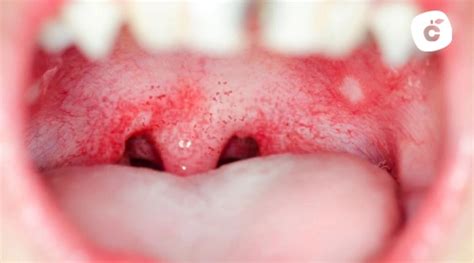

Manchas Rojas en el Paladar

Con frecuencia, muchos pacientes acuden a la consulta tras manifestar molestias o notar la aparición de manchas rojas en el paladar. La aparición de manchas rojas en el paladar puede ser alarmante. Si te ha pasado, debes saber que antes de entrar en pánico lo importante es determinar las posibles causas para dar con el tratamiento indicado.

Las manchas rojas en el paladar no aparecen por una sola causa específica. De hecho, son diferentes las variantes que pueden determinar su aparición, porque la sintomatología de estas se diferencian por el tipo de patología.

Son diferentes los tipos de manchas en el paladar y se distinguen según los síntomas y patologías.